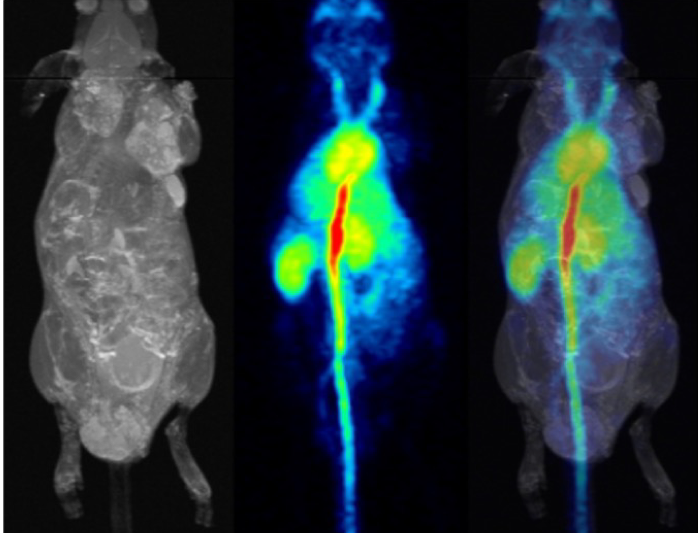

pmod’s tools provide comprehensive workflows for post-processing and quantification of imaging data for fundamental oncology research, development of radiotracers and theranostics, and in clinical research studies. Imaging scientists can trust pmod to reproducibly read their data, interpret the meta-data/units and help users calculate statistics such as SUV for their studies and publications.

For treatment evaluation and theranostic development